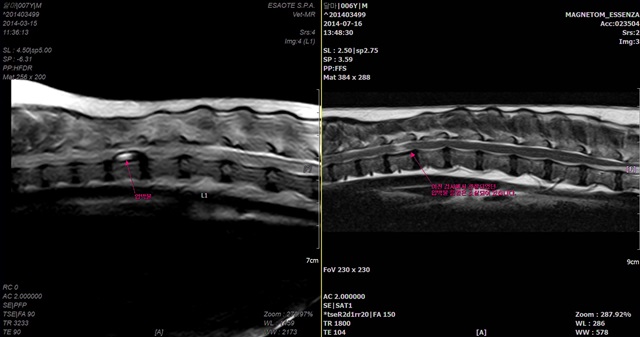

후지마비로 지역 병원에서 한 달 반 동안 스테로이드를 처방 받았지만 차도가 없어 내원한 ‘달마’는 MRI 촬영 시 척수실질을 크게 압박하는 이물이 관찰됐다.

이미 신경손상 병변도 보여 개선 가능성이 거의 없다고 판단됐지만, 이물 제거 수술 없이 침과 한방으로만 3개월간 치료함으로써 증상을 크게 개선시킬 수 있었다.

나조차도 달마가 한방치료로 척추병변에 변화가 있었는지 너무 궁금했다. 증상개선 후 MRI 필요성을 느끼지 못하는 보호자를 설득해 내 돈 주고 MRI를 재촬영 했을 정도였다.

정상생활이 가능할 정도로 회복됐다(오른쪽) (사진 : 강무숙 원장)